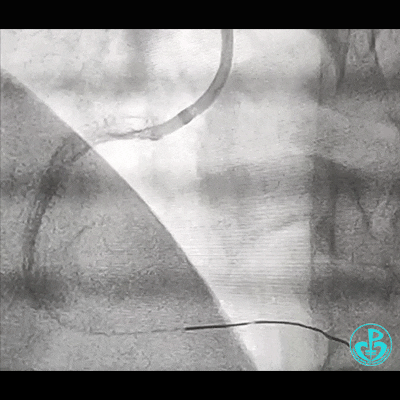

处理右冠,XB RCA,Sion、Sion blue导丝,2.0×20mm球囊。支架植入过程相当顺利,很快就完成,窃喜!心想后扩后马上结束!

导丝怎么扩右冠近段弥漫性病变中远段闭塞顺利开通并植入支架,哪知道故事才刚刚开始!!!_https://www.jmylbn.com_新闻资讯_第4张

导丝怎么扩右冠近段弥漫性病变中远段闭塞顺利开通并植入支架,哪知道故事才刚刚开始!!!_https://www.jmylbn.com_新闻资讯_第5张

植入3.5×29mm和3.5×24mm支架。